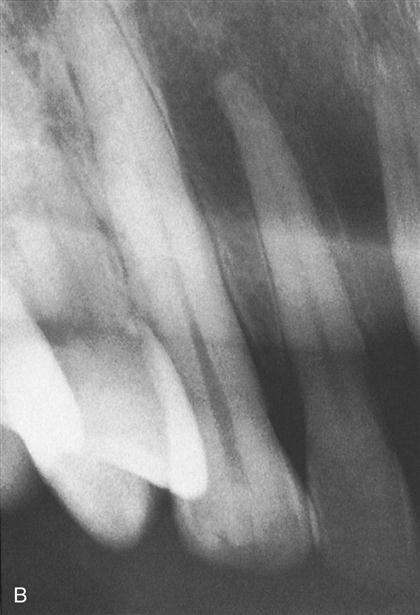

Intraoral Film

Film specifically designed for taking dental x-rays inside the mouth.